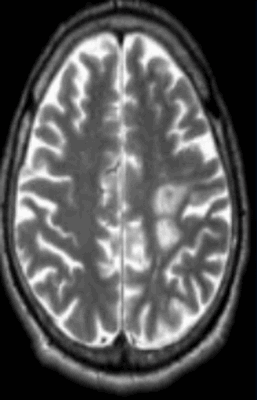

Рассеянный склероз на МРТ головного мозга выглядит как пятна округлой формы диаметром до 2 сантиметров, которые по мере развития патологии могут сливаться. Оттенок измененных участков зависит от стадии болезни и бывает светлым, темным или идентичным здоровым тканям (без контраста не выделяется).

“Пальцы Доусона” на МР-томограммах в аксиальной (слева) и сагиттальной (справа) проекциях - выглядят на Т1 ВИ как светлые продолговатые очаги

Классическим признаком рассеянного склероза на МР-снимках головного мозга являются бляшки линейной формы, располагающиеся перпендикулярно боковым желудочкам. Их называют “пальцы Доусона”.